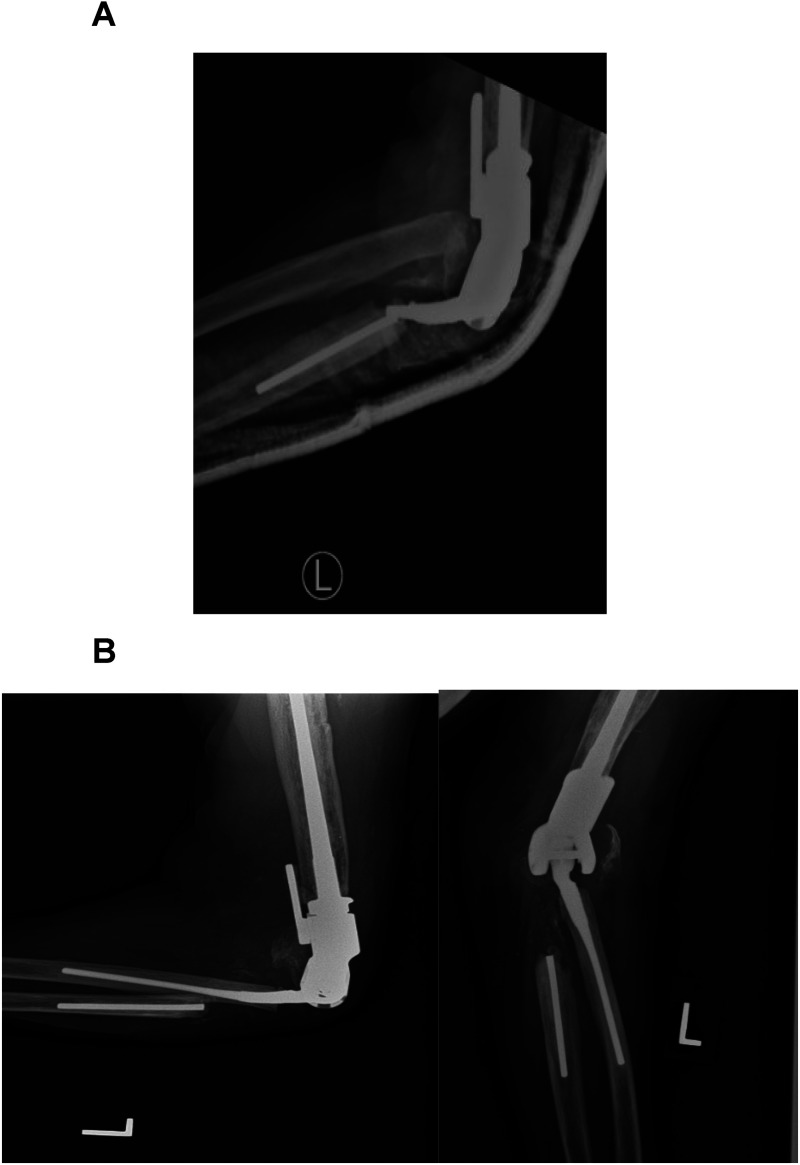

As the number of total elbow arthroplasty (TEA) continues to increase worldwide, one might predict the number of revision TEA would rise as well. The most common indications for revision TEA include (a) loosening, (b) infection, and (c) periprosthetic fracture. Although the rate of revision TEA procedures continues to rise due to the infrequency in which they are performed compared to other arthroplasty surgeries, no gold standard algorithm or procedure for managing severe ulnar bone loss in revision TEA has been determined. Various surgical techniques and strategies including allograft-prosthesis composite, custom long prosthesis with or without allograft, and resection arthroplasty have all been employed in attempting to address severe ulnar bone loss in revision TEA. Though the reported outcomes are mixed at best between each treatment strategy with similar complication rates. Another option is implanting the ulnar component into the radius. In those patients with severe ulnar bone loss, a humeroradial TEA revision can provide stability, restore range of motion, and provide pain relief.

Abstract Image